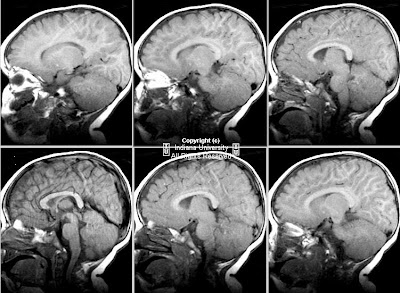

Findings

Figure 3 and Figure 4: Sagittal T1 postcontrast and T2-weighted MR images reveal a dilated terminal thecal sac without a tethered cord. Benign subtle scalloping of the posterior margin of the lumbar and sacral vertebral bodies (Figure 4) is best visualized on the T2-weighted images.

Figure 5 and Figure 6: Axial T1 postgadolinium and axial T2-weighted MR images reveal a dilated thecal sac with root sleeve prominence.